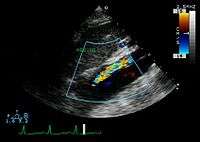

Transesophageal ultrasound

The transesophageal echocardiogram (TEE) is a relatively good test in the diagnosis of aortic dissection, with a sensitivity up to 98% and a specificity up to 97%. It has become the preferred imaging modality for suspected aortic dissection. It is a relatively noninvasive test, requiring the individual to swallow the echocardiography probe. It is especially good in the evaluation of AI in the setting of ascending aortic dissection, and to determine whether the ostia (origins) of the coronary arteries are involved. While many institutions give sedation during transesophageal echocardiography for added patient comfort, it can be performed in cooperative individuals without the use of sedation. Disadvantages of TEE include the inability to visualize the distal ascending aorta (the beginning of the aortic arch), and the descending abdominal aorta that lies below the stomach. A TEE may be technically difficult to perform in individuals with esophageal strictures or varices.

-

Aortic dissection with a intramural hematoma as seen on TEE